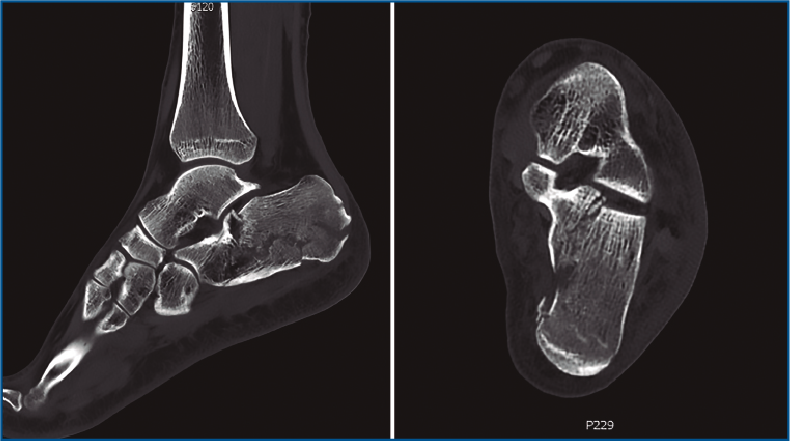

Primero, realizamos limpieza de tejidos blandos y localizamos el flexor hallucis longus (FHL), que será el límite medial de seguridad. Recordamos que, en las fracturas de grado II de Sanders (Figuras 1 y 2), permanece íntegro un gran fragmento anteromedial, mientras que el fragmento posterolateral se desplaza. Tras la limpieza, identificamos la fractura (Figura 3) y movilizamos el fragmento lateral. Luego cambiamos los portales e introducimos el artroscopio por el portal medial, que nos permite acceder hasta el seno del tarso y visualizar el ligamento interóseo talocalcáneo. A través de un pequeño abordaje en la cara lateral del calcáneo reducimos la articulación subastragalina posterior (Figura 4A).

Figura 1. Fractura del calcáneo Sanders IIA.

Figura 2. Fractura del calcáneo Sanders IIB.